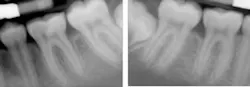

A 12-year-old African American female presented for treatment of localized rapidly progressive periodontitis on No. 19 and No. 30 prior to orthodontic treatment. Prior dental care included prophys and sealants. The LANAP protocol was performed at one appointment with local anesthetic.

Miss Novice before the LANAP protocol.